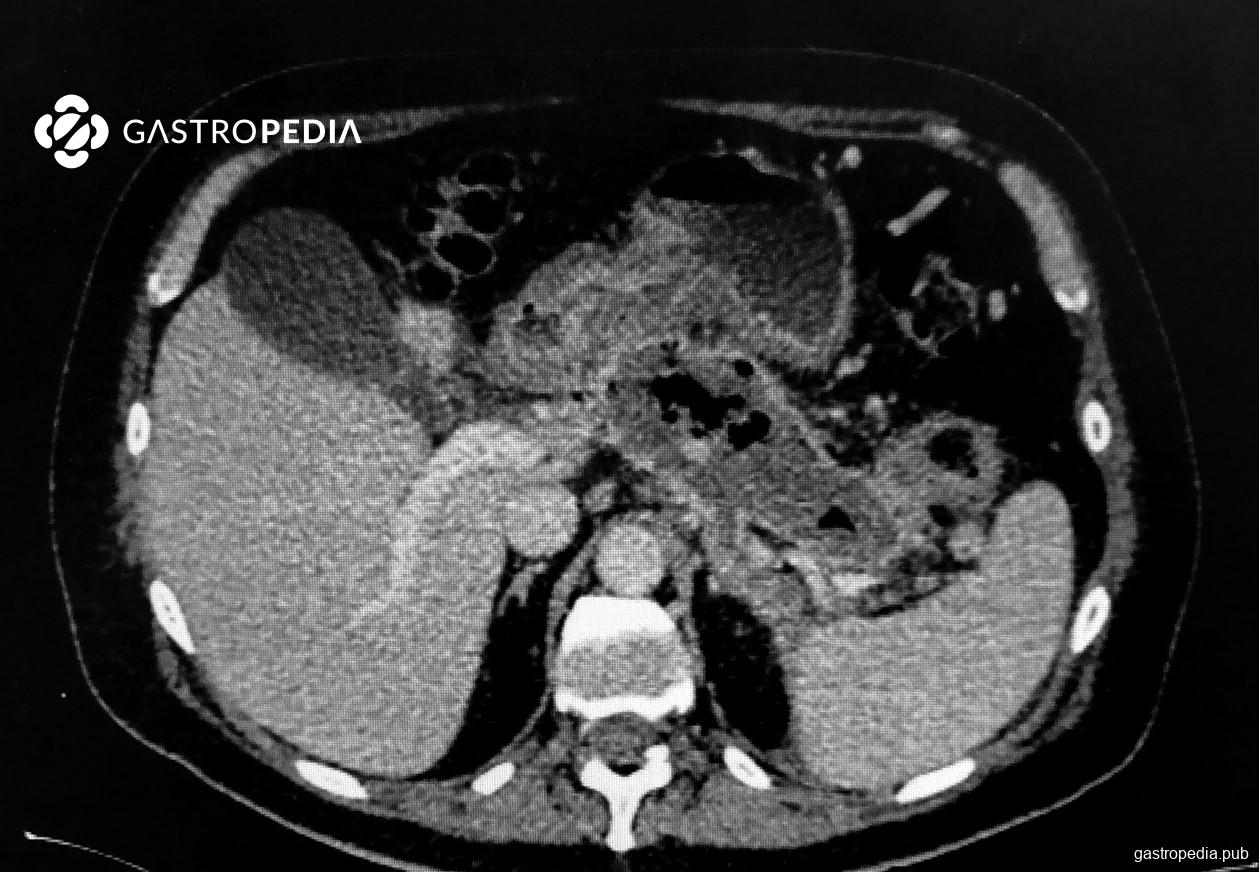

Após 10-14 dias, no caso das pancreatites moderadamente graves e graves, pode haver formação de tecido necrótico. Neste momento podem surgir sinais e sintomas que indiquem infecção desse tecido. O uso de terapia com antibióticos deve ser considerado na suspeita ou confirmação de infecção de tecido necrótico. A confirmação pode ser feita através de imagem (presença de gás em topografia da necrose é um sinal inequívoco de infecção) ou através de exames laboratoriais e piora clínica (febre, aumento de PCR, leucocitose, ou cultura de material com presença de microrganismos).

Imagem de arquivo pessoal, autorizada pelo paciente